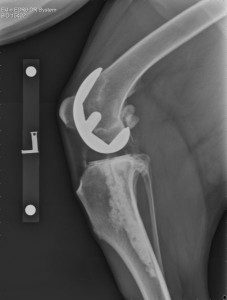

The commercial system consists of a polyethylene (plastic) component that is fixed to the tibia and a metal component that is fixed to the femur. The two components articulate with each other, creating a new weight-bearing surface and mimicking the movement of a normal joint during knee motion. The commercial total knee replacement system is suitable for dogs >15kg body weight. It is, however, reliant on the stabilising ligaments of the knee joint, known as the collateral ligaments – on the outside and inside of the knee – being intact for your dog to be suitable for a commercial total knee replacement; the cruciate ligaments do not need to be.

During surgery, the stifle joint (knee) is exposed through an incision on the side of the knee. The joint surfaces of both the femur and tibia are removed and replaced by two components. In the commercial system, a metal component is used to replace the damaged joint surface of the femur and an ultra-high molecular weight polyethylene (UHMWPE, plastic) implant is used to replace the damaged joint surface of the tibia; both components are fixed using orthopaedic cement. As the success of the commercial surgical system relies on the supporting ligaments of the knee, these ligaments are thoroughly checked prior to completion of the surgery.